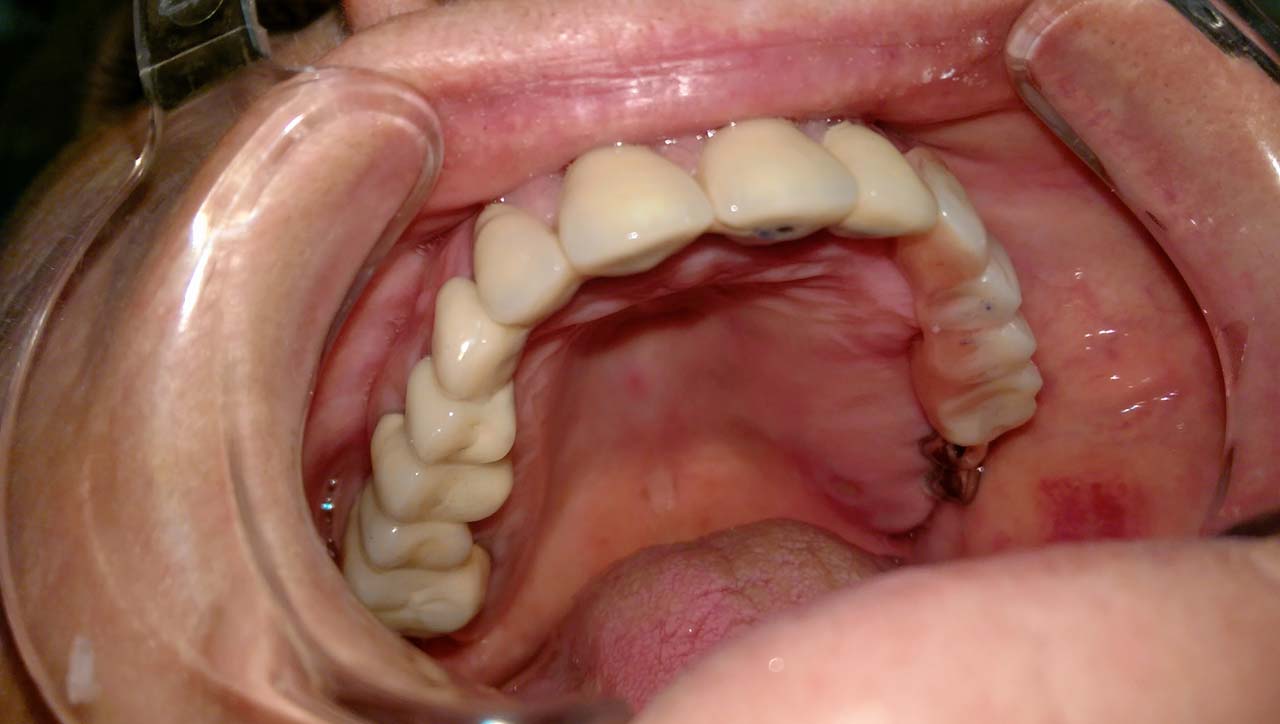

Teljes fogatlanság helyreállítása 2 nap alatt

Teljes fogatlanság helyreállítása 2 nap alatt azonnal terhelhető svájci IHDE implantátumokkal és PMMA műanyag hidakkal. Intraorális szkennerrel vettünk lenyomatot az implantáció után, és erre a digitális mintára készítette el a fogtechnika a hidak digitális tervezését, majd faragta ki műanyagból. Ezt a gyors munkát az azonnal terhelhető implantátumok és a digitális lenyomat, tervezés segítségével tudtuk megcsinálni mindössze 2 nap alatt. Dr. Kelemen Péter és a Symbion Fogtechnika munkája.